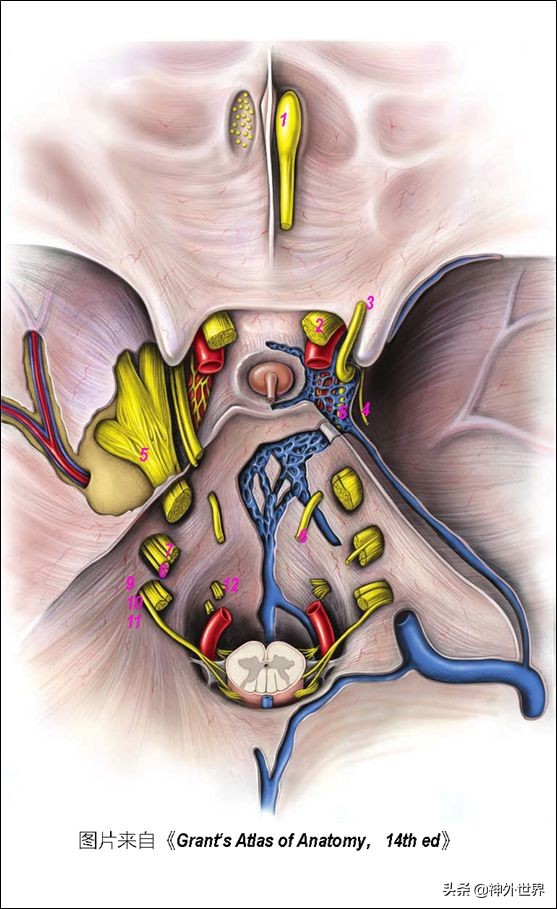

- 脑干的内外腔室:①内有导水管,上通第三脑室、下入其背侧的第四脑室,并经第四脑室的正中孔和外侧孔与蛛网膜下腔相同。②周围一圈扩大的蛛网膜下腔就是脑池(环绕中脑的——脚间池、环池、四叠体池;脑桥前的——桥前池;脑桥外侧的——桥小脑角池;延髓前的——延池;延髓后的——小脑延髓池)。

三、脑干的供血动脉

- 脑干供血——异: ①中脑:BA顶端、近端PCA。②脑桥:BA、AICA。③延髓:ASA、VA、PICA。

- 脑干供血——同:①旁正中穿支;②短旋支;③长旋支。

四、脑干与小脑之间的三个裂隙和三个神经血管复合体

- 中脑小脑裂——三叉神经小脑上动脉复合体。——第四脑室顶壁上半部与中脑顶盖之间。

- 脑桥小脑裂——小脑前下动脉-面听神经复合体——第四脑室外侧隐窝开口于此。

- 延髓小脑裂——小脑后下动脉-后组颅神经复合体——第四脑室顶壁下半部。